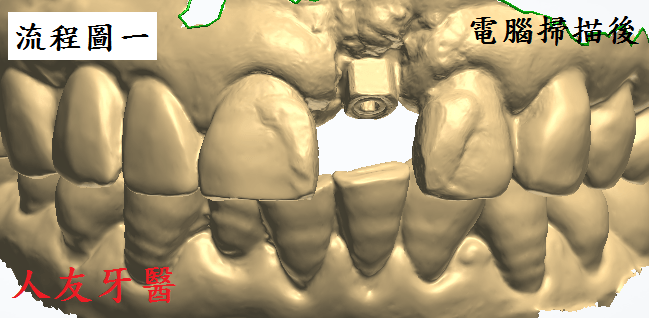

埋入植體後,待植牙骨密度到達標準值後再利用電腦掃描製作全鋯牙冠膺復

電腦掃描製作流程圖